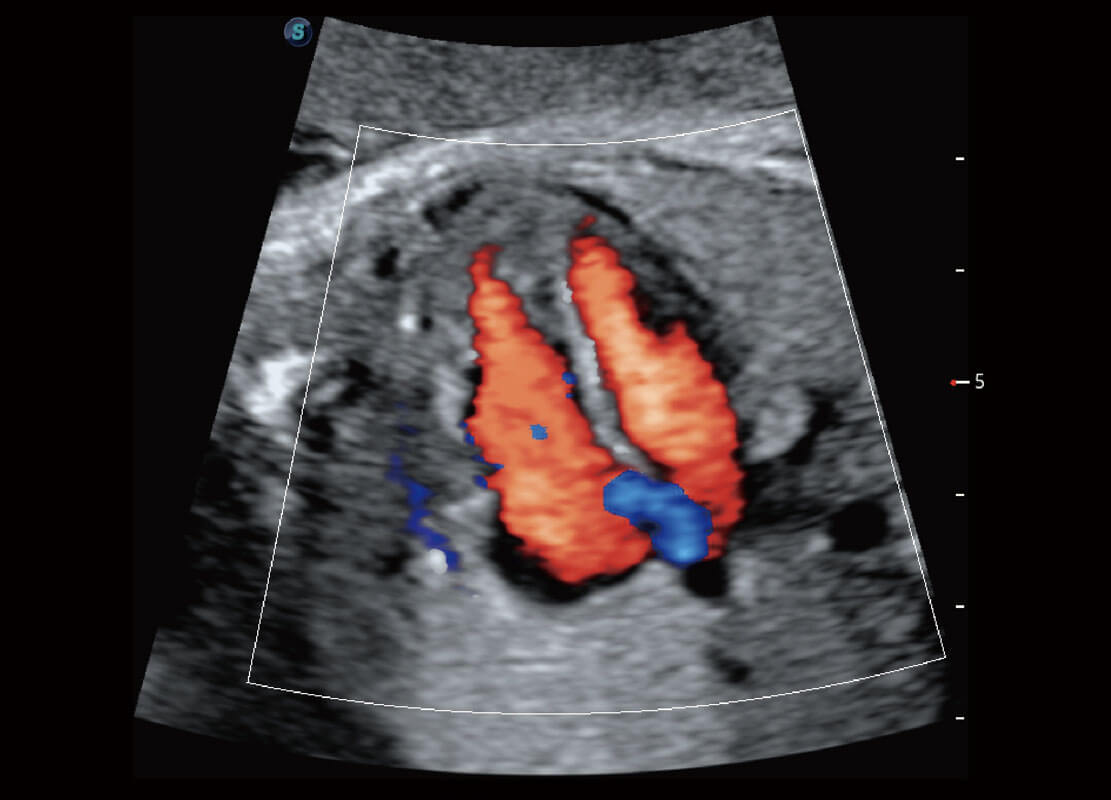

胎心筛查

P60搭载一系列胎儿心脏成像技术,实现精细的胎儿心脏评估。

• 右室双出口